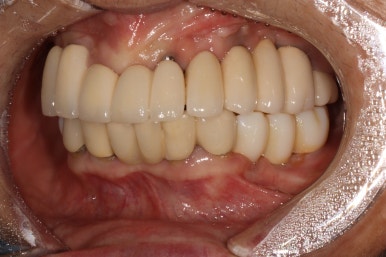

차이를 별로 못느끼실 수 있겠지만, 임플란트 보철물 완성 6개월 후 방문 때 구강내 사진입니다.

감사히도 환자분께서 상당히 깨끗하게 유지하고 계셔서, 잇몸에 염증하나 없이 너~무 보기 좋더라구요.

어금니 우측

좌우측 측면 사진 비교시, 아래 어금니 임플란트로 깔끔하게 메꿔진 빈 공간이 인상적입니다!